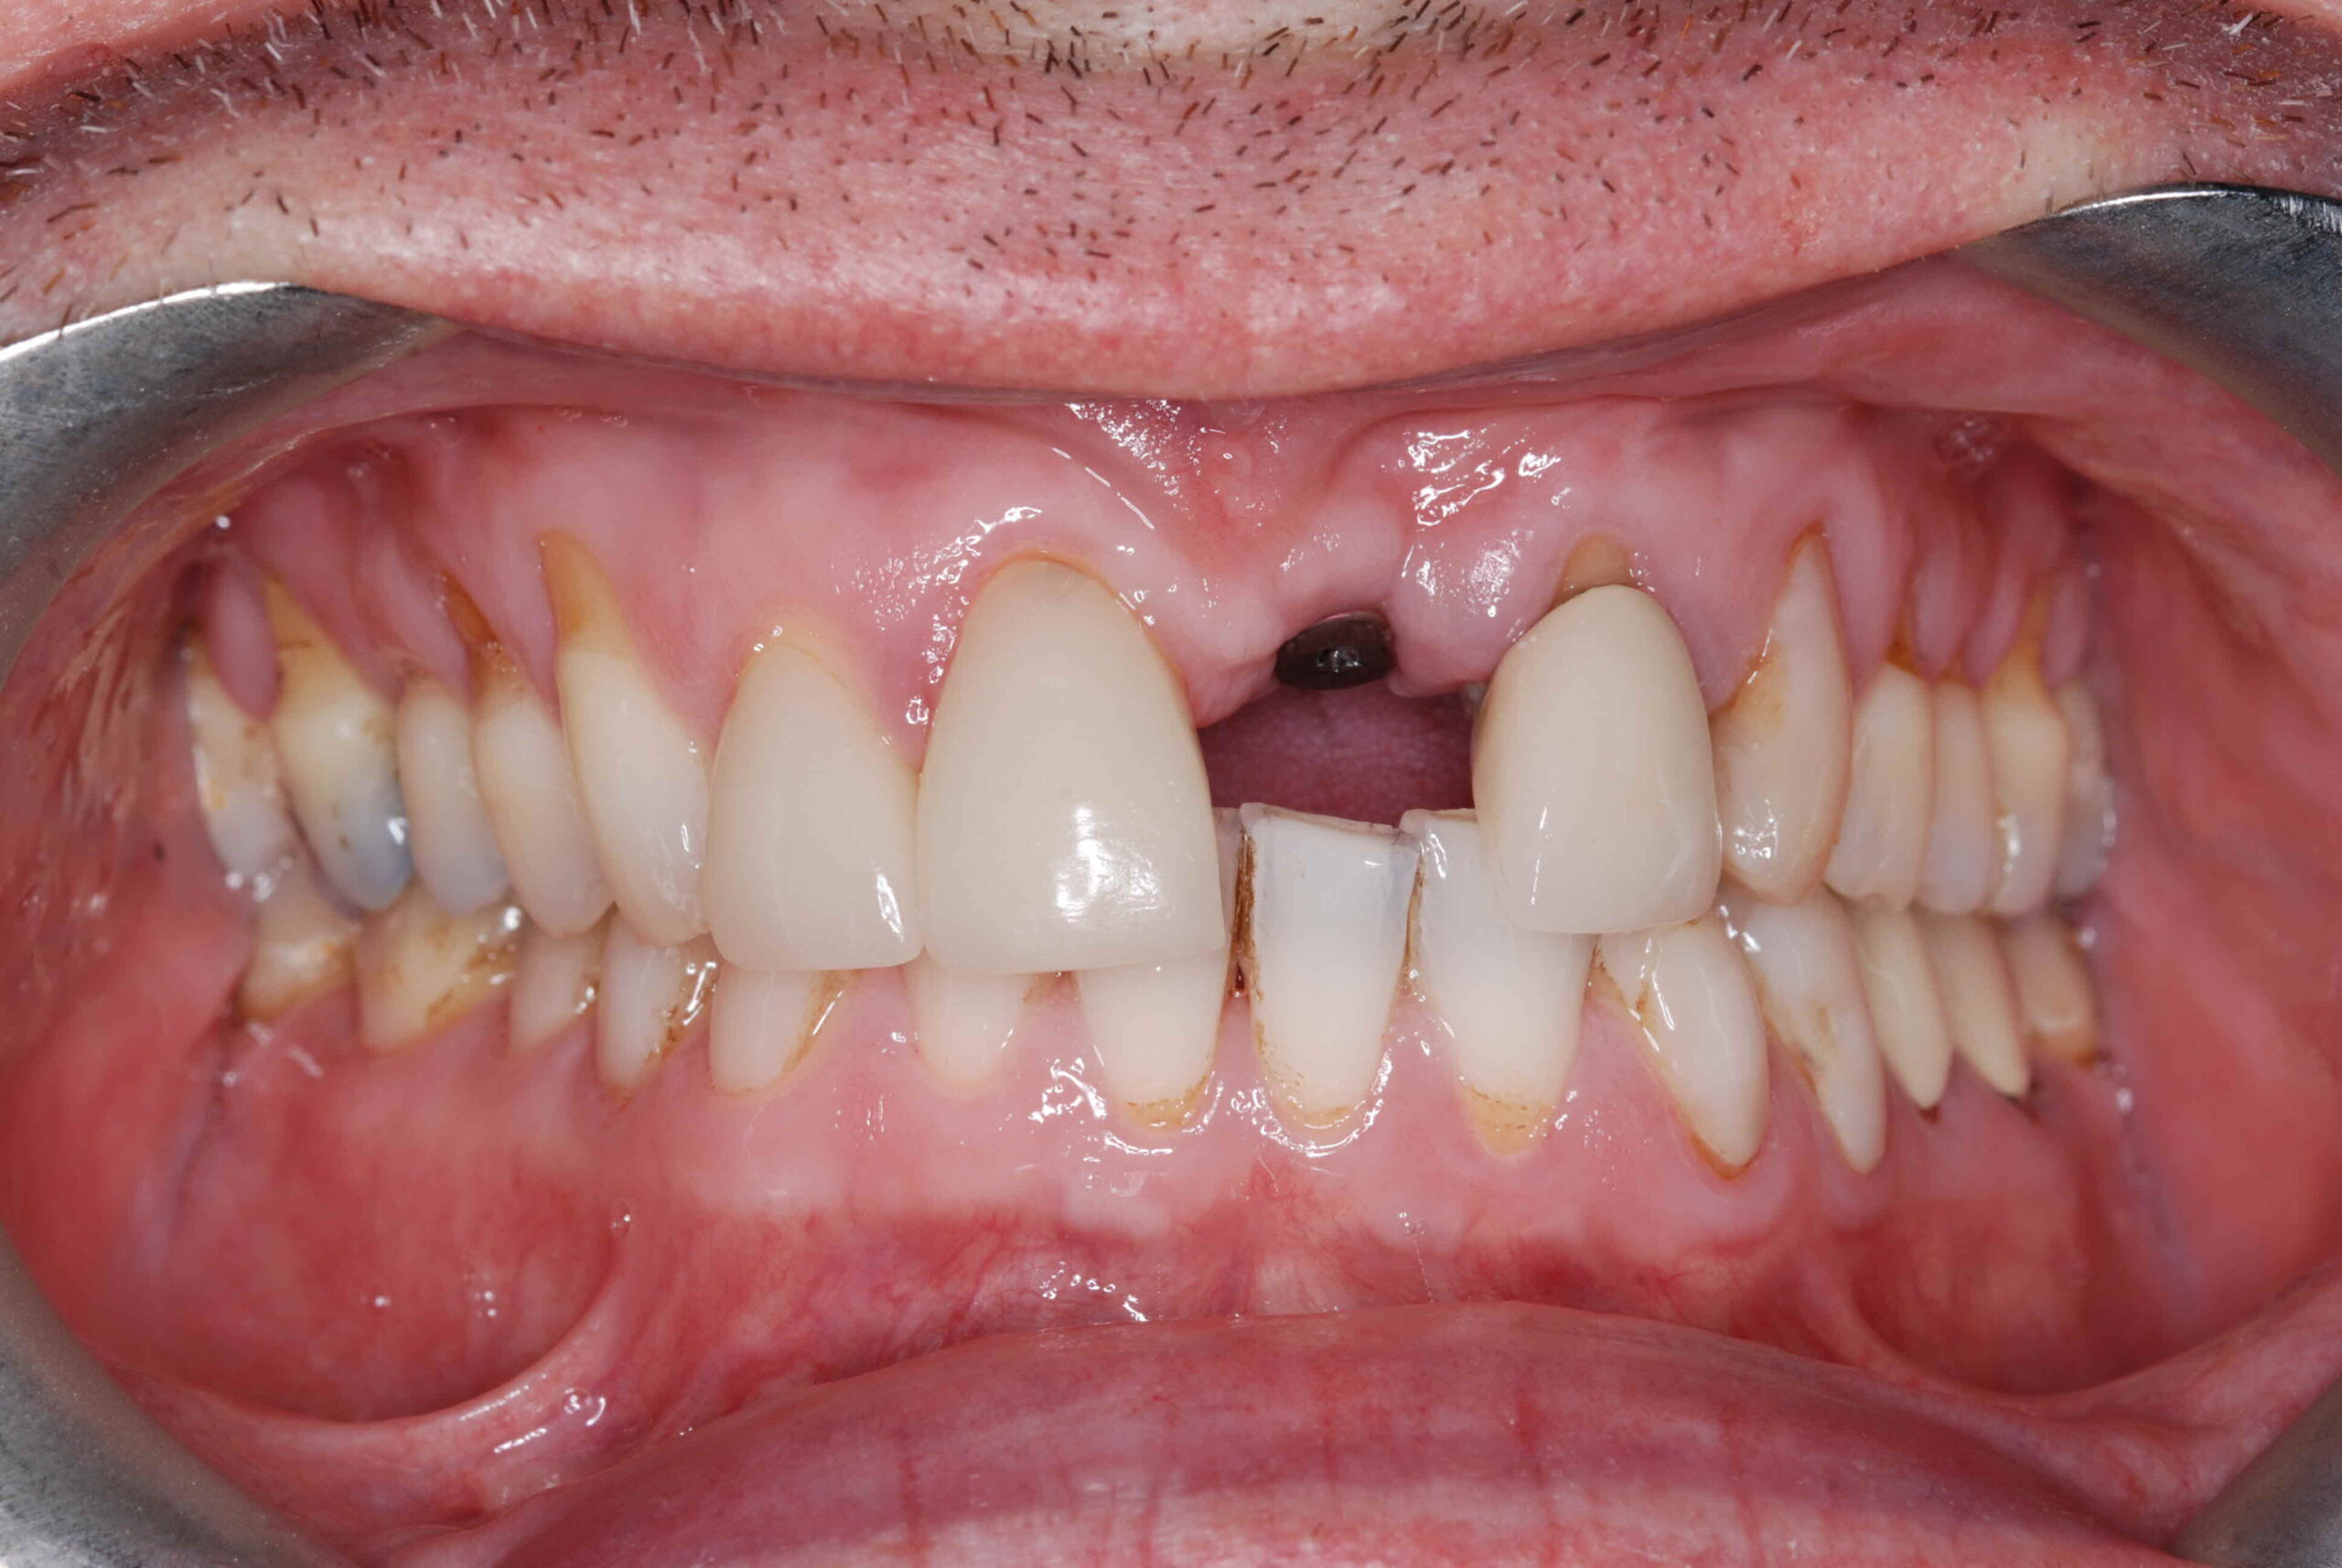

Losing a tooth often leads to there being a visible gap between the other teeth which can be unsightly and upsetting. Conventional dentistry such as dental bridges involves drilling into adjacent teeth that may be perfectly healthy. Implants avoid the need to drill into any other teeth, and therefore avoid possible complications such as infection, fracture, and ultimately the loss of these teeth.

Dental implants can be used to replace a single missing tooth, multiple teeth, or all teeth.